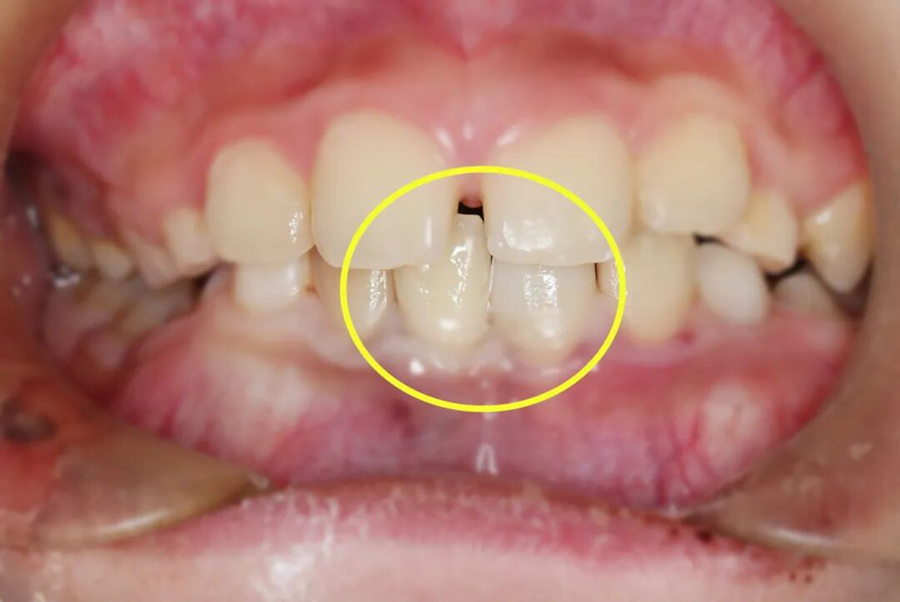

“牙齒脫落時間越久,再植成功率越低,每一分鐘都很關鍵!”口腔中心接診后,立刻啟動急救模式??趦?nèi)檢查和拍片檢查發(fā)現(xiàn),小千脫落的牙齒牙根完整,折斷的牙齒已露髓(可見紅點出血)。

第一步,牙齒再植

救治團隊小心翼翼地接過家長帶來的脫落牙齒,用專業(yè)工具輕柔清理牙根表面的污染物,確保不損傷牙根組織,隨后精準將牙齒植入原來的牙槽窩,再用特制纖維帶將其與相鄰健康牙齒緊密結(jié)扎固定,為牙齒重新愈合提供穩(wěn)定支撐,整個再植過程一氣呵成。